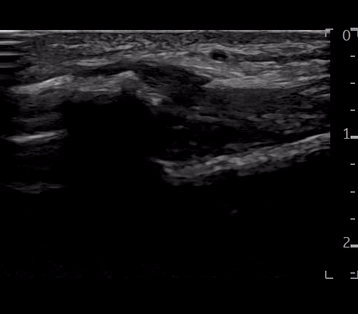

위 이미지는

의표준 경혈 초음파 영상인데요.

노란 화살표로

표시한 부분이

앞쪽 거골과 비골을 연결하는입니다.

표준 경혈 초음파상

*1) 비슷한 두께로

*2) 직선으로 주행하면서

3) 인대 내부 섬유 패턴이

보여야 하죠.

정상 혈자리와 다른게

보이시나요?

표준 경혈 초음파와 달리

1) 전거비인대가 두껍게부어있고*

**2)구불구불 주행하고요.*

3) 노란색 화살표 친인대 내부에 까만 틈이 보입니다.